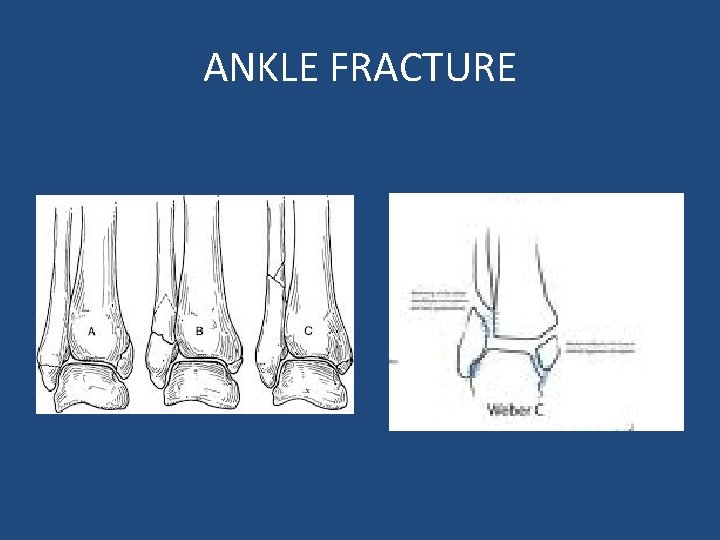

ANKLE FRACTURE

• Intact medial malleolus: – Weber A: • splint + NWB X 6 weeks. • Early ROM. – Weber B/C: • If medial joint line widen: ORIF. • If not: ? – If both malleoli are broken: • ORIF